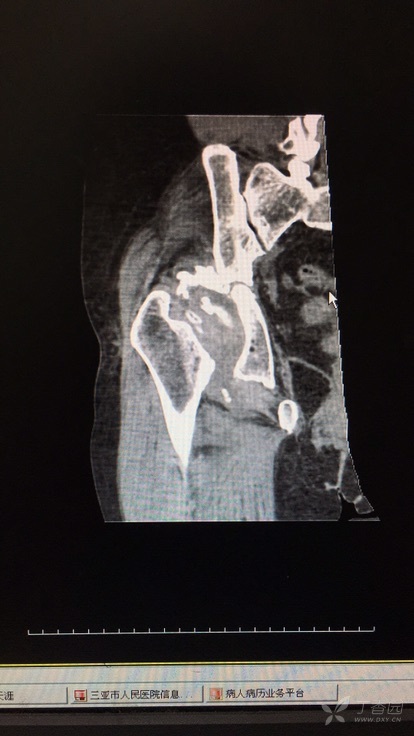

交通事故伤残鉴定需要拆除内固定吗?保持骨折的位置和稳定性,促进骨折愈合。很多经过内固定手术的当事人就会有一个疑问,我身体里面还有钢钉钢板,能带着内固定鉴定吗?还是说... 但需要注意的是,细则规定了四肢骨折邻近关节经内固定术治疗后,若依肢体关节活动受限程度可能评定为九级以上伤残者,须拆除内固定后进行...